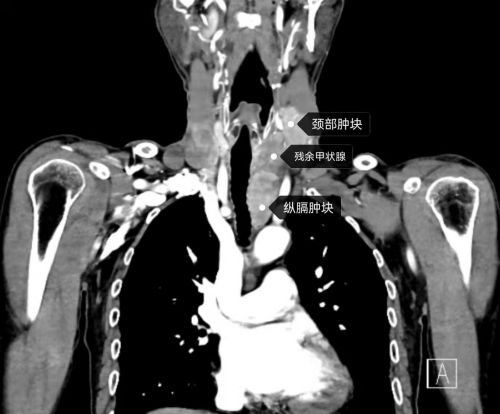

ct显示:双侧甲状腺残余腺体内多发肿块并与气管、食管分界不清,左颈部、纵膈内多发肿块。

入院后的CT和MRI检查显示:双侧甲状腺残余腺体内多发肿块并与气管、食管分界不清,左颈部、纵膈内多发肿块,考虑“多发淋巴结转移”。